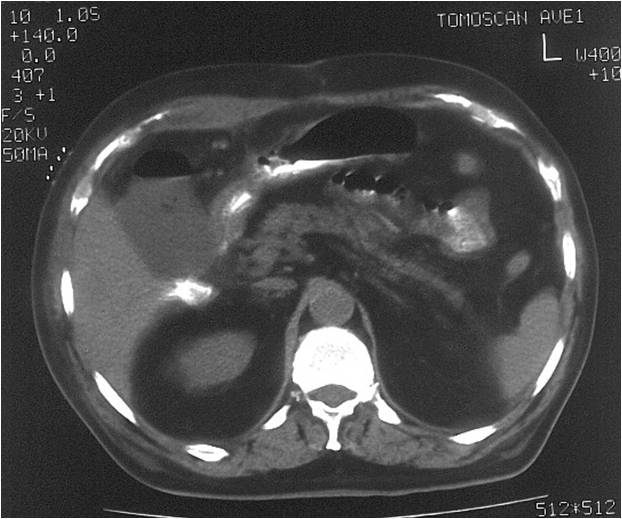

- Abscess post right hemicolectomy

- Successful placement and drainage